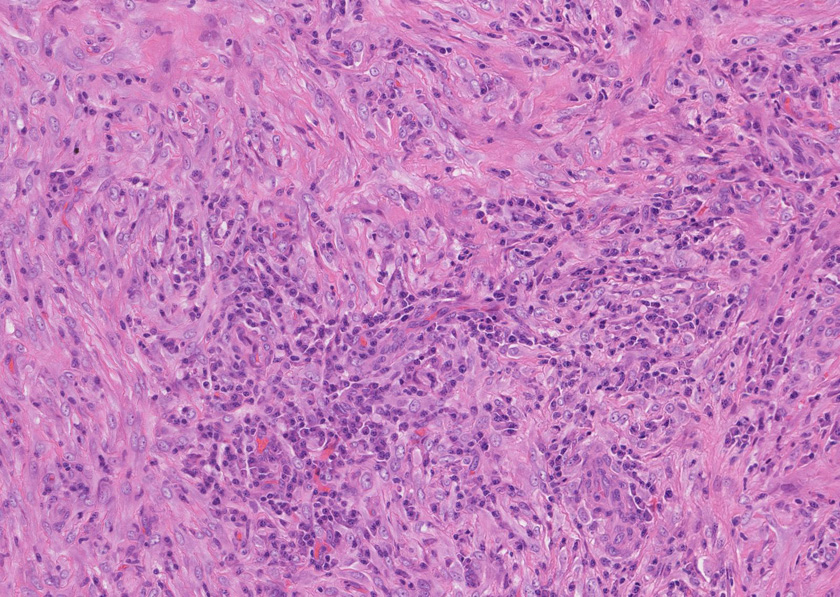

線維化組織に類円, 葉巻型淡明な核の紡錘型細胞が増生している。免染SMA陽性。血管周囲に慢性炎症あり。

組織像は膵腫瘤B, Cと同じくinflammatory myofibroblastic tumorである。島状に形質細胞主体の慢性炎症が強い。腹膜腫瘤には腺管は認められない。